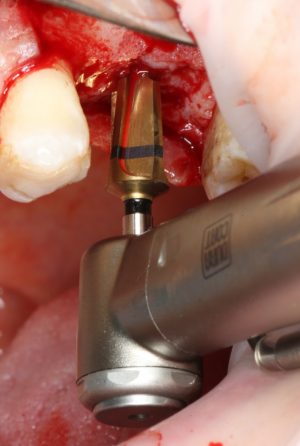

Следующей мы используем фрезу 2.0/3.2:

Такие фрезы — особенность имплантационной системы Astra Tech. Они нужны для того, чтобы не разломать края лунки и сделать переход между фрезами (а мы переходим с 2.0 на 3.2 мм) более точным и плавным, благодаря направляющей 2.0 мм. Однако, пройти лунку такой фрезой на всю глубину удаётся далеко не всегда. В таких случаях используется обычная спиральная фреза диаметром 3.2 мм (с зеленой полоской). Но в нашем случае такой необходимости нет, ибо выше только субантральное пространство, поэтому мы работаем только вот такой двойной фрезой.

Если бы мы хотели поставить имплантат диаметром 4.5 мм, то далее мы перешли бы к кортикальной конической фрезе. Однако ж, я посчитал, имплантат диаметром 5.0 мм в данной клинической ситуации будет более надежным и органичным, поэтому мы продолжаем подготовку лунки. И следующая используемая фреза — 3.2/3.7 — то же самое. что и предыдущая, с направляющей 3.2 мм: